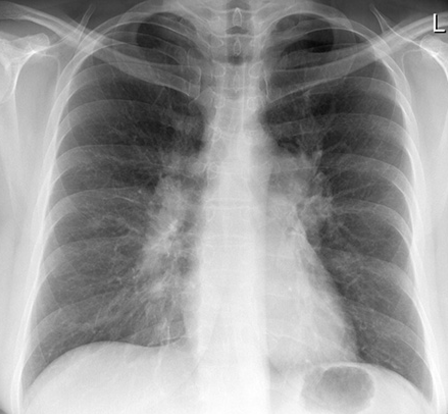

lingular pneumonia

L heart border obscured L hemidiaphragm intact